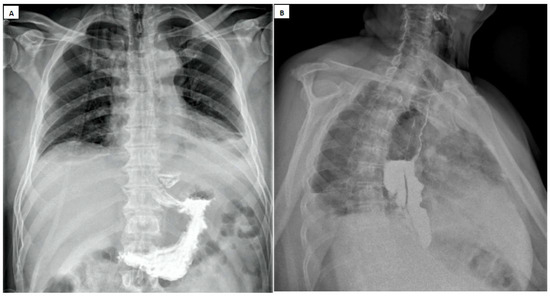

- It depends on the availability of qualified, experienced personnel, who may not always be accessible overnight;

- Patient transport to the radiology department, patient cooperation (related to their level of consciousness), correct positioning during the procedure, and swallowing ability are all factors influencing the accuracy of the examination and can be compromised in critically ill patients;

- Barium swallow studies carry a risk of aspiration and pulmonary edema, and residual contrast material in the esophagus may compromise the quality of subsequent upper digestive endoscopy [89].